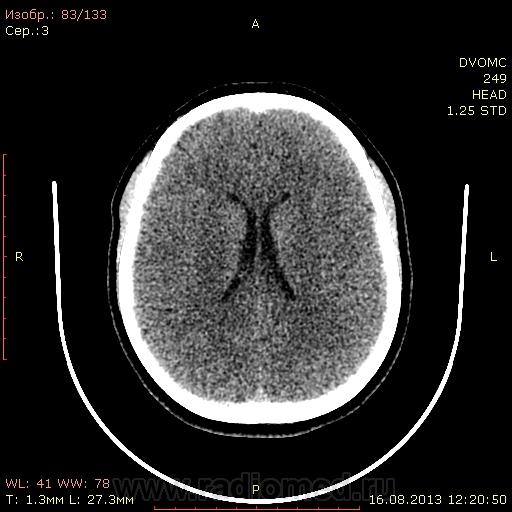

21 год. На момент исследования жалоб нет. DICOM здесь http://files.mail.ru/062AC0004DF8471CAC95B38693A0153C

Что за уплотнение в базальных ганглиях слева? Мелкое начинающееся обызвествление? В таком возрасте?

Нет ли сужения борозд? Прошу оценить их глубину т.к. у самого еще не сформировалось чисто визуальная мера(только третьи мозги в моей практике

Обызвествление базальных ядер в таком возрасте-норма.

Третьи мозги, говорите. Не переживайте. КТ достаточно грубый метод, при травме в мозгу что-то видно только у больных, доставленных в кабинет на каталке. Такие борозды и должны быть у непъющего молодого человека. И обызвествление базальных ядер, тоже клинического значения не имеет (по крайней мере, не встречал). Правда, есть еще синдром Фарра, но то другой случай, там, в первую очередь идет клиника. Какой-то странный у вас протокол, наверное на SDH (субдуральную гематому). Желательно добавить в протокол восстановление из сырых данных с другим фильтром и другой толщиной (например, 5мм).